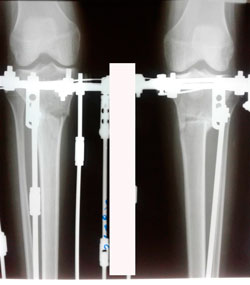

Исходник - 29 лет.

Дата операции - 13.08.2020

перед крутками

на фиксации

Дата снятия аппаратов - 17.11.2020